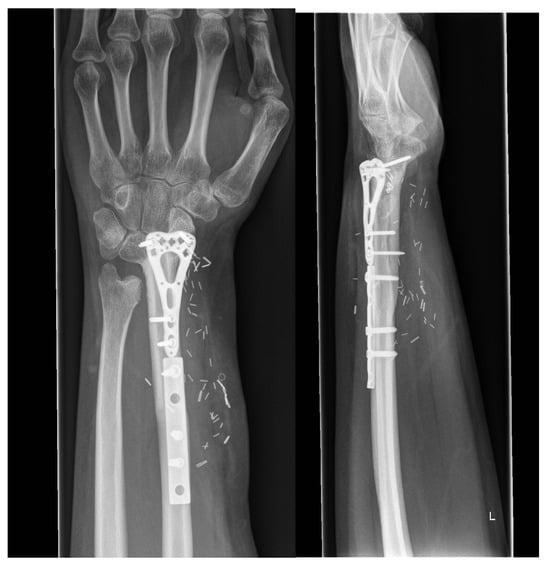

3.4. Group 4: Fusion of Scaphoid, Lunate, Fibula and Radius (RFSL-Fusion)

| GROUP 4 | Case 5 | Distal radius involving the radiocarpal surface | Sarcoma, secondary osteoblastoma | 61 | 20 | 9 | Vascularized fibula | RFSL-Fusion | N/A N/A | 25-0-30 50-0-60 | 70% | MMWS = 65 DASH = 24 | yes |

| Case 6 | Distal radius involving the radiocarpal surface | Giant cell tumor | 72 | 45 | 6 | Vascularized fibula | RFSL-Fusion | 60-0-60 70-0-70 | 30-0-30 70-0-50 | 80% | (N/A) | yes | |

| Case 7 | Distal radius involving the radiocarpal surface | Giant cell tumor | 25 | 38 | 8 | Vascularized fibula | RFSL-Fusion | 50-0-50 90-0-50 | 40-0-0 80-0-70 | 80% | (N/A) | yes | |

| Case 8 | Distal radius involving the radiocarpal surface | Giant cell tumor | 6 | 40 | 7.5 | Vascularized fibula | RFSL-Fusion | 70-0-70 80-0-80 | 30-0-10 50-0-50 | 60% | (N/A) | yes |